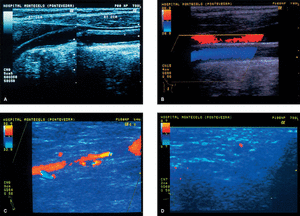

Figura 1. A) Ultrasonidos modo B: engrosamiento circuferencial homogéneo y difuso de la pared de arteria carótida común (entre cursores). B) Ultrasonografía en color de la arteria carótida común sin evidencia hemodinámica de estenosis. C) Ultrasonografía en color de la arteria axilar, que demuestra estenosis de más del 50%, de 2 cm de longitud, con un jet de alta velocidad en la posición distal (color azul). D) Ultrasonografía en color de la arteria temporal. Un plano transversal demuestra un halo hipoecoico alrededor de la luz del vaso (color rojo).

Con la sospecha posterior de arteritis de grandes vasos, se realizó una eco-Doppler en color de troncos supraaórticos y sus ramas, y se objetivaron cambios estructurales de la pared de las arterias carótida común y axilar izquierda (fig 1A-C). Una angiografía de troncos supraaórticos y de arteria axilar izquierda mostró la existencia de estrechamiento de la luz del vaso de la arteria axilar por engrosamiento de la pared afectada. Con la posibilidad de AT se realizó una eco-Doppler de la arteria temporal izquierda, y se visualizó un halo perivascular compatible con el diagnóstico clínico (fig. 1D). La biopsia de la arteria temporal demostró los hallazgos característicos de la enfermedad.